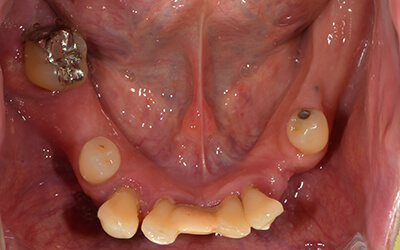

【歯周病で多数歯欠損① 】営業職で入れ歯では仕事が厳しくなった患者様

患者さま情報:40代 男性

治療期間:6ヶ月

治療費:4,920,630円(税込み)

リスク:骨が足りない場合は骨を足す骨造成が必要です。

副作用:手術により腫れや痛みを伴うことがあります。

before